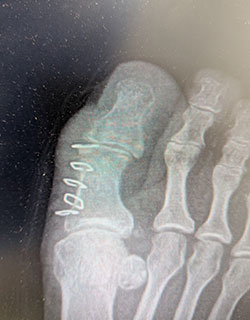

Hallux rigidus (severe arthritis of the big toe joint) causing painful, limited motion of the joint and requiring removal of the arthritic bone and partial joint replacement (hemi-arthroplasty) to allow full range of motion and return to weight bearing.

Before SurgeryBefore

After SurgeryAfter